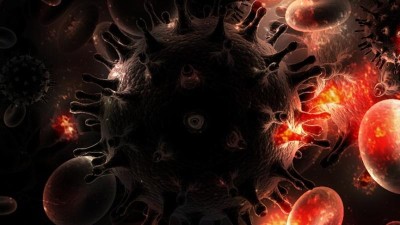

„K nehodě došlo 17. srpna mezi obcemi Patokryje a Lužice. Řidič osobního vozu předjížděl čtyři další auta. Náš kamarád Mára v tu chvíli jel na motorce a tento řidič jej srazil. Mára skončil s otevřenou zlomeninou, zdravotníci se snažili na poli najít kus kolene, aby mu tu nohu mohli dát dohromady. Po pár týdnech ale bylo jasné, že mu nohu musí vzít," popsala stručně tragický příběh Martina Vítková.

Marek stále neměl vyhráno, po amputaci jej čekala další operace ruky a druhé nohy. „Domů jej pustili 17. září, tedy měsíc po nehodě. Teď se učí být samostatný, rehabilituje. To vše stojí mnoho peněz, byli bychom šťastní, kdyby mohl získat kvalitní protézu, aby se mohl zase postavit na obě nohy," uzavírá Martina Vítková.